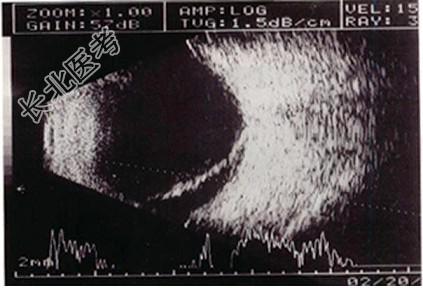

- 单项选择题患者眼前闪光,视力减退1周。结合超声声像图, 最可能的诊断是   (   )

A、局限性视网膜脱离

B、完全性视网膜脱离

C、玻璃体后脱离

D、局限性脉络膜脱离

E、以上均不对